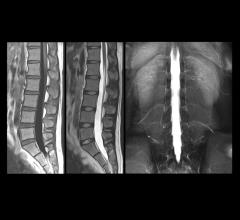

Fetuses with enlarged ventricles — the fluid-filled cavities inside the brain — determined by magnetic resonance imaging (MRI) scans may be less likely to benefit from surgery in the womb to treat spina bifida, according to a National Institutes of Health-supported study.